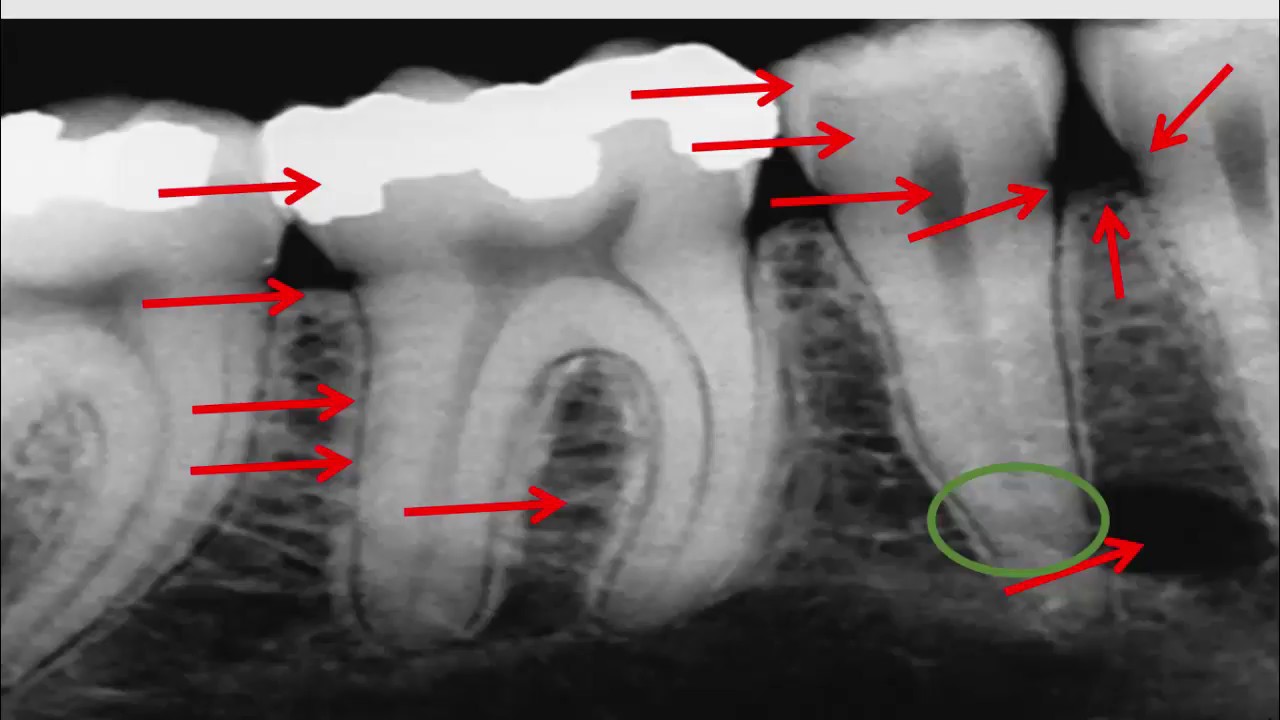

Les bitewings sont une radiographie dentaire qui montre les couronnes des dents supérieures et inférieures dans une zone spécifique de la bouche. Ils sont généralement utilisés pour détecter les caries interproximales, c'est-à-dire les caries qui se forment entre les dents et ne sont pas visibles à l'œil nu. Les bitewings permettent également de détecter les anomalies dentaires telles que les dents mal alignées et les infections des racines des dents.

Lors d'un examen dentaire, le dentiste peut recommander des bitewings pour évaluer l'état de santé des dents et des gencives. Les bitewings sont réalisés en plaçant une pellicule radiographique à l'intérieur de la bouche, contre les dents supérieures et inférieures. Le patient mord alors sur la pellicule, ce qui permet de prendre une image des dents et des gencives. Les bitewings sont indolores et ne nécessitent pas d'anesthésie.

Les bitewings sont généralement recommandés tous les 1 à 3 ans, en fonction de l'état de santé bucco-dentaire du patient. Ils sont un outil précieux pour la détection précoce des caries interproximales et des problèmes dentaires qui pourraient autrement passer inaperçus.